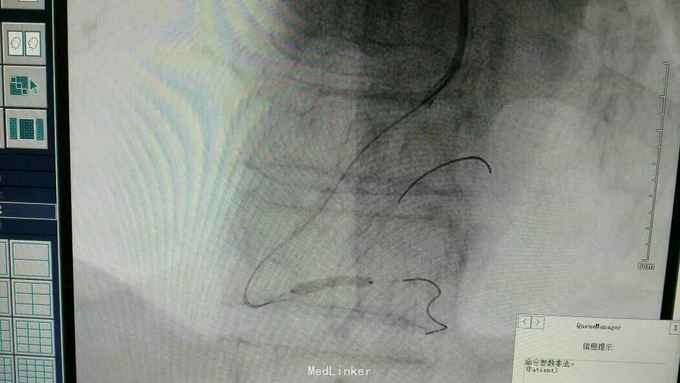

急性下壁心肌梗死,立即启动绿色通道,行急诊冠脉造影明确冠脉病变,必要时PCI治疗,行CAG示:LAD中重度狭窄,LCX尚可,RCA中段局限重度,可见前向血流,选段后降支处重度狭窄,血管钙化明显。考虑此次靶血管为RCA中段处,血管钙化迂曲明显,拟处理RCA,术中导丝到达远端后,预扩球囊反复高压扩张后,支架均无法通过,采用双导丝增加支撑依然无法通过,再更换高压后扩球囊高压扩张,锚定等,最终成功植入支架

急性心梗有时候处理相对较容易,但此病变在于血管钙化迂曲明显,且再次详细阅片后发现局部有“礁石”样病变,预扩球囊及后扩球囊不易扩张,有时需切割或旋磨,但对于急性心梗,如果血流达到理想级别,可不勉强处理,急性心梗中,有些病变为固定狭窄基础上急性血管闭塞,处理并非如一般血栓病变那样容易,造影后仍然需要详细阅片,根据具体病变情况选择合适手术处理方法